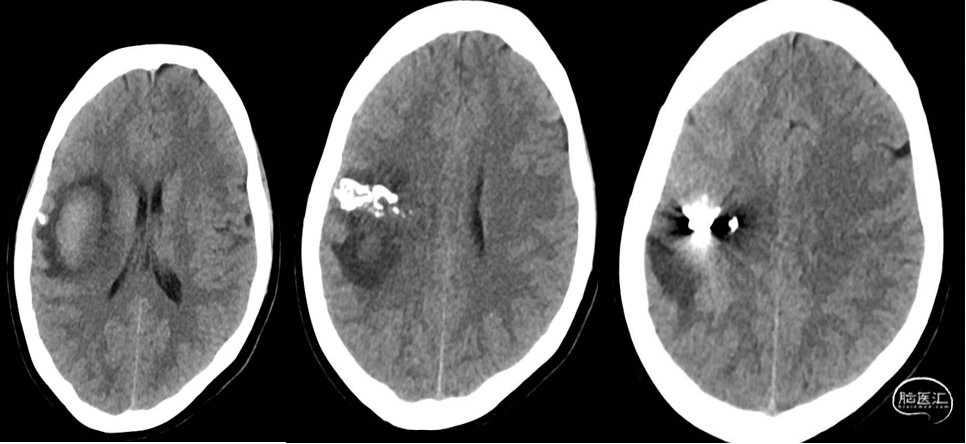

患者诉20余天前因“突发左上肢无力”,至当地医院就诊,行头颅CT检查后拟“脑出血”住院治疗,行脑血管造影检查发现“脑血管畸形”,经治疗,左上肢乏力逐渐好转;今为进一步治疗“脑血管畸形”来我院,门诊以“脑血管畸形”收入院。自发病以来,患者精神、食欲逐步恢复,进食可,大小便正常,体重无明显改变。

我院磁共振